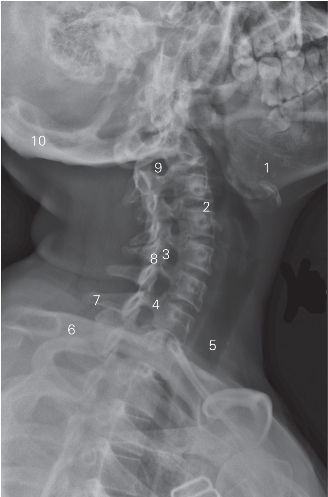

图6-3 颈椎斜位DR平片

1 下颌骨 lower jawbone

2 第3/4颈椎间隙 3rd/4th cervical intervertebral space

3 上关节突 superior articular process 4 椎弓板 lamina arcus vertebrae

5 气管 trachea 6 锁骨 clavicle

7 棘突 spinous process 8 下关节突 inferior articular process

9 第2/3颈椎间孔 2nd/3rd cervical foramen intervertebrale

10 枕骨 occipital bone